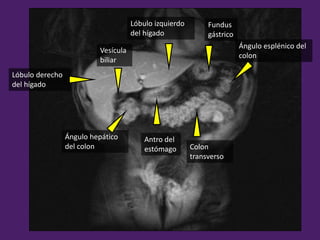

Ángulo esplénico del

colon

Ángulo hepático

del colon Colon

transverso

Lóbulo derecho

del hígado

Lóbulo izquierdo

Fundus

gástrico

Vesícula

biliar

Antro del

estómago

Vena renal Izquierda

Arteria mesentérica

superior

Tronco

celíaco

Vena cava Inferior

ascendente